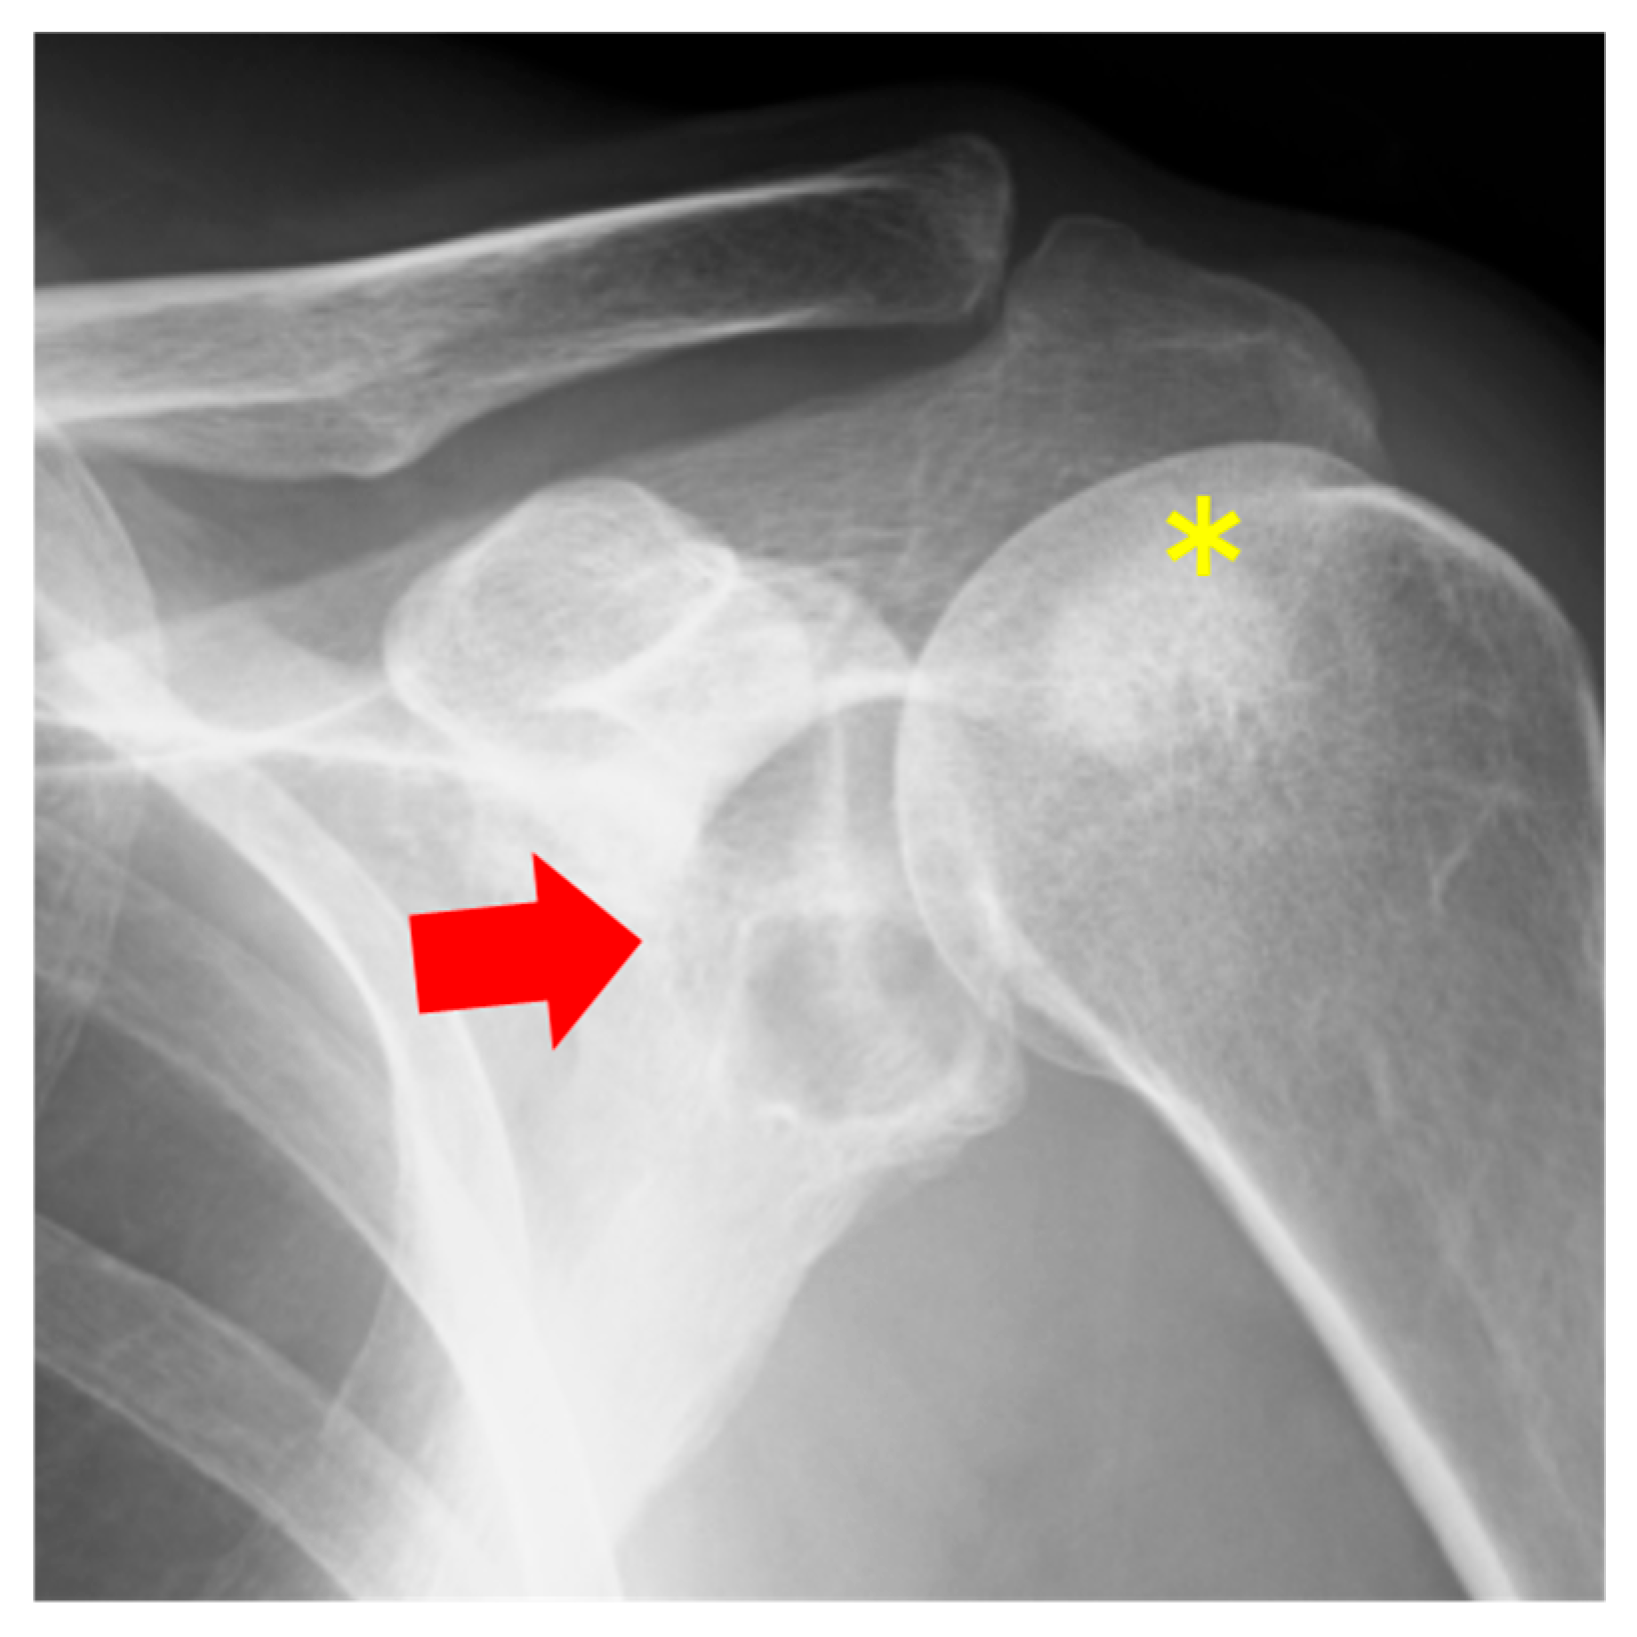

2.1. Case 1

2.2. Case 2